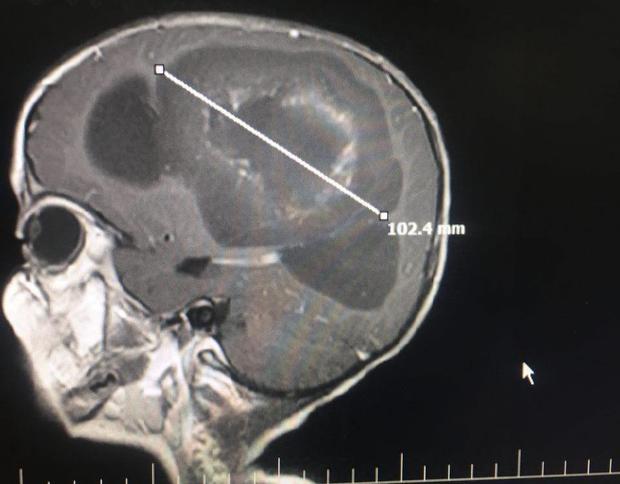

به گزارش روز شنبه ایرنا به نقل از روابط عمومی دانشگاه علوم پزشکی، خدمات بهداشتی و درمانی قزوین، دکتر مهران مرادی متخصص جراحی مغز و اعصاب در خصوص این اقدام درمانی گفت: این کودک به دلیل داشتن تومور مغزی از ناحیه دست راست دچار فلجی شده بود.

وی همچنین اظهار کرد: این عارضه همچنین بر قدرت تکلم این کودک نیز تاثیرگذاشته بود.

دکتر مرادی اضافه کرد: حین عمل جراحی، به دلیل نبود دستگاه ناویگاسیون امکان برداشت کامل تومور از مغز کودک نبود که بعد از عمل در ام آر بدون وجود این دستگاه 80 تا 90 درصد از آن برداشته شد.